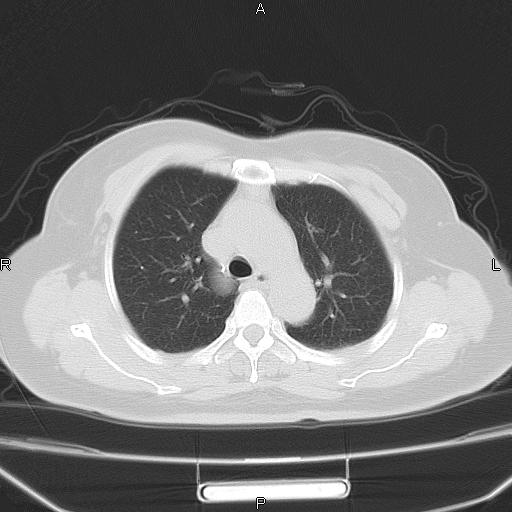

胸腺瘤

女、63Y 双眼睑下垂,早轻晚重。 胸腺瘤???

结果胸腺瘤